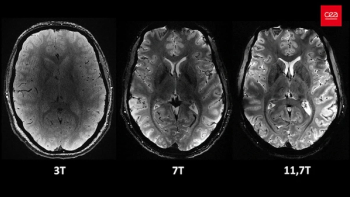

As ongoing advances continue to redefine and elevate the diagnostic capabilities of MRI, ensuring the safety of patients and operators through effective signage, training and regular safety audits is of paranount importance.